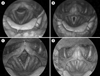

Results: A 41-year-old man presented with progressive breathy dysphonia. His brother had mitochondrial myopathy. Biopsy of the biceps muscle demonstrated cytochrome C oxidase-negative ragged blue fibers confirming mitochondrial myopathy. Videostroboscopy showed marked vocal fold atrophy, but subsequent injection laryngoplasty did not significantly improve the patient's voice, despite improved postoperative glottic closure.